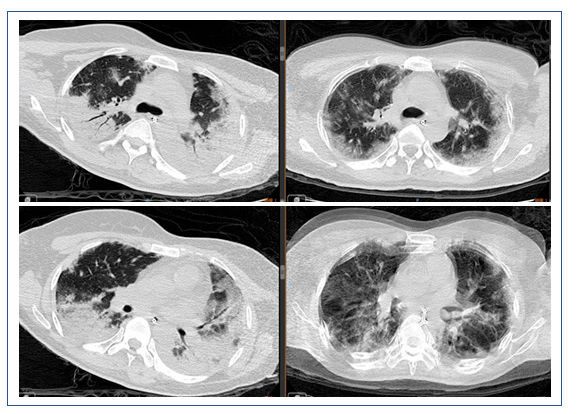

2019年1月16日复查胸部CT:双侧中下肺实变影较1月9日增多(图7)。

图7 患者复查胸部CT与前对比

左:2019年1月16日CT;右:2019年1月9日CT

患者1月4-6日使用激素,然后停用,胸部CT显示部分病变加重,部分病变被吸收;另外,中下肺背部实变比较明显,而且气管和支气管征比较突出,另外,病变沿着气管、支气管束的分布,符合机化性肺炎表现。但是机化性肺炎不能引起类似呼吸衰竭如此严重的情况,所以个人考虑是否为纤维素性机化性肺炎(AFOP),当然需要病理诊断来进一步明确。患者淋巴细胞非常低,这是目前很难解释的,所以还是期待进一步的检查。

该患者的实变处于整个重力依赖区,从双上肺的后段到下面的背段。一方面可能是停用激素后的反弹,另外一方面考虑跨肺压过小,与长期仰卧位机械通气有关,另外,PEEP过高对患者也有不良影响。此类患者如果不用激素,可以考虑俯卧位通气,能够短期迅速缓解患者重力依赖区的实变。我们还是期待后续的检查结果。